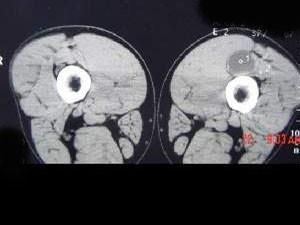

问题 男,48岁,左大腿上段后部轻度胀痛,轻压痛,无明确外伤史,请结合所提供的图像,选择最佳选项 ( )

选项 A、腱鞘囊肿 B、腱鞘脓肿 C、皮脂腺瘤 D、脂肪瘤 E、表皮样囊肿

答案 A